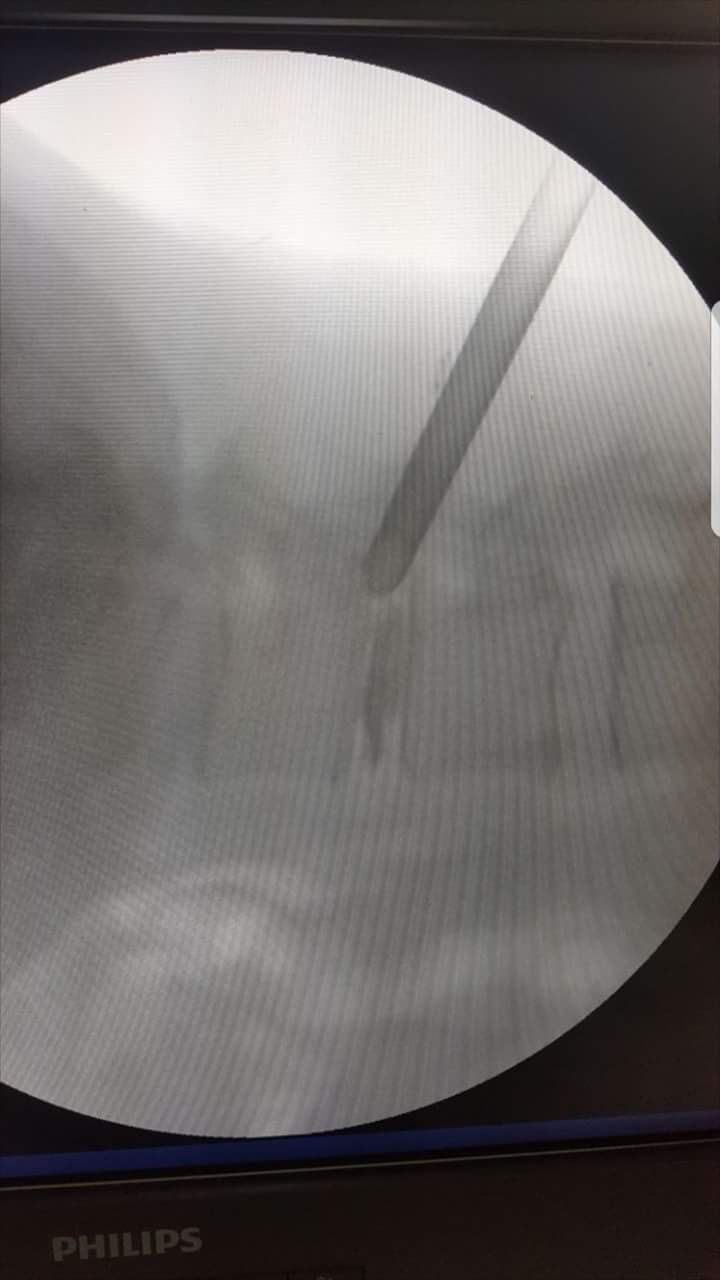

Endoscopic discectomy under Local Anaesthesia.

Big L5 S1 disc causing severe pain in left leg

Removed disc fragment in awake n aware anaesthesia.

Patient was watching the whole procedure at screen and was responding to commands.

Skin incision was just 6 mili meter

No stitch required at end of procedure

Biggest advantage of this procedure is that since patient is awake he will not allow surgeon to injure any neural structure

Safe Spine Surgery

Dr. I P AGRAWAL, SHALBY HOSPITAL, JAIPUR